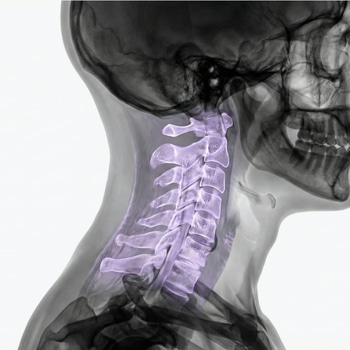

Bilateral foraminal stenosis is a condition in which the nerve’s “exit hole” in the spine is narrower on both sides, which can irritate the nerve roots and cause radiating pain, numbness/tingling, and sometimes weakness. This is often experienced in the legs and feet when the lumbar spine is affected – or in the arms and hands when the cervical spine is affected.

MRI Cervical spine

• MRI Cervical Spine – detailed imaging diagnostics of vertebrae, discs, spinal cord and nerves in the neck.

• Suitable for pain, numbness, weakness or stiffness in the neck, shoulders and arms.

• Shows changes that are not detected with regular X-rays – completely without radiation.

• Fast and safe examination with referral and response from a specialist within a few days.